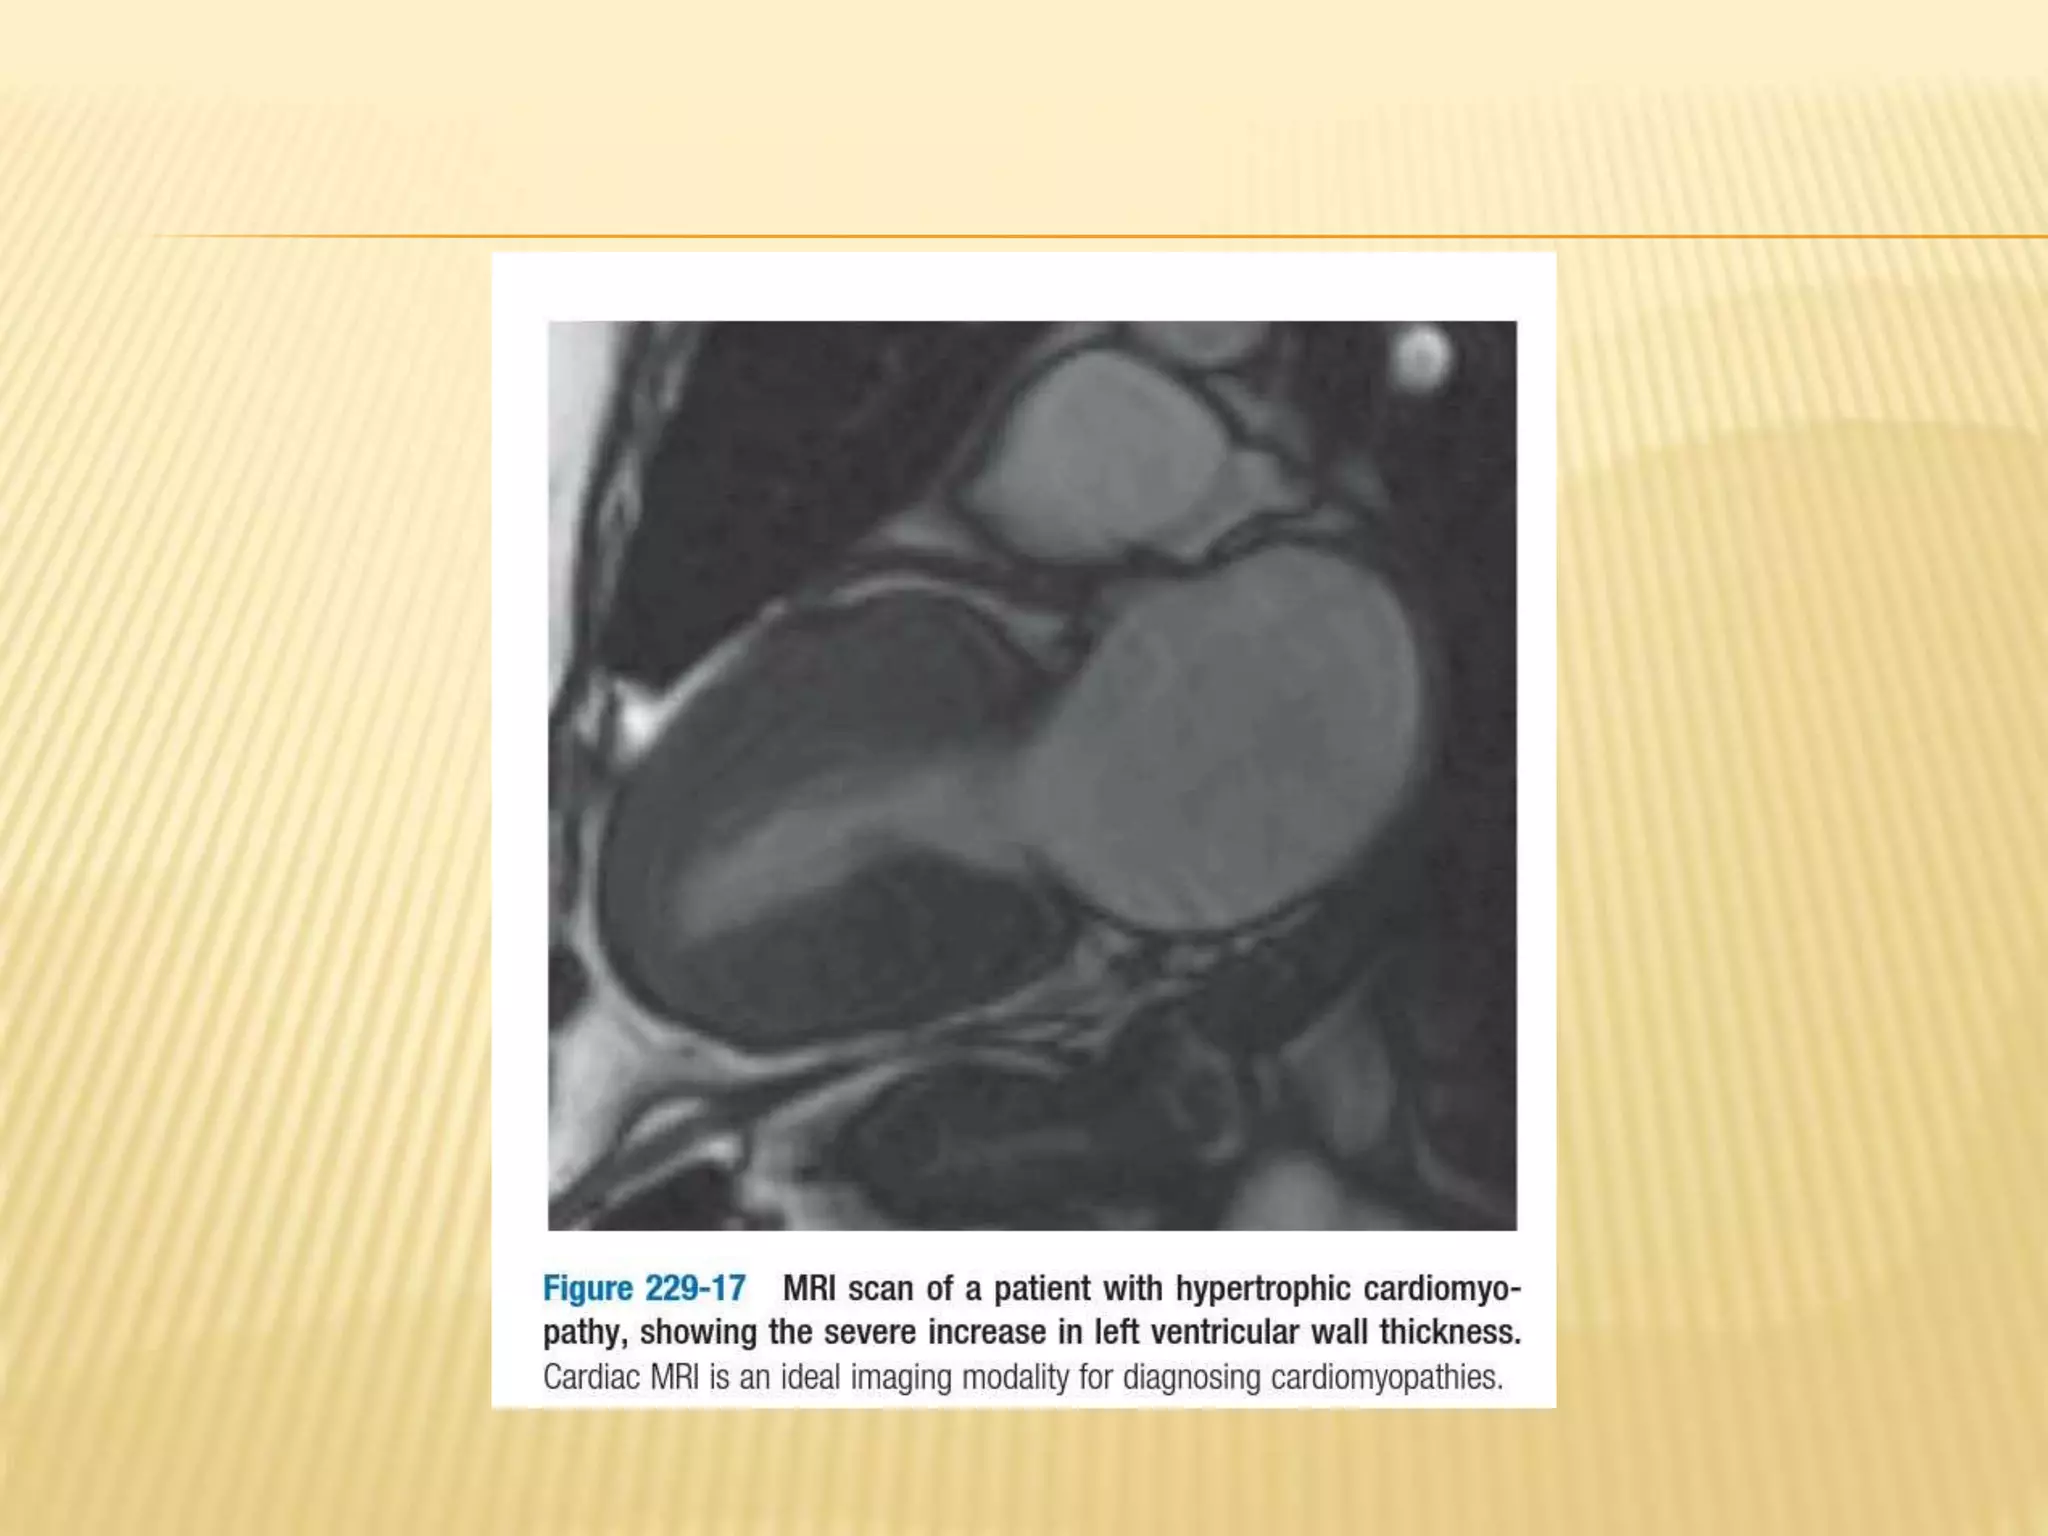

MRI IMAGING

 Principle- based on magnetic properties of

hydrogen nuclei.

 Larger vessels can be visualised on mri

without contrast agents, gadolinium is

frequently employed as contrast agent to

produce magnetic resonance angiograms.

 Both static and cine images can usually be

obtained using electrocardiographic

triggering, often within short breadth holds of

10-15secs.

 MRI is of great value in defining anatomic

relationships in patients with complex

congenital heart disease and

cardiomyopathies

MRI IMAGING  Principle-based on magnetic properties of hydrogen nuclei.  Larger vessels can be visualised on mri without contrast agents, gadolinium is frequently employed as contrast agent to produce magnetic resonance angiograms.  Both static and cine images can usually be obtained using electrocardiographic triggering, often within short breadth holds of 10-15secs.

• 51.

 MRI isof great value in defining anatomic relationships in patients with complex congenital heart disease and cardiomyopathies